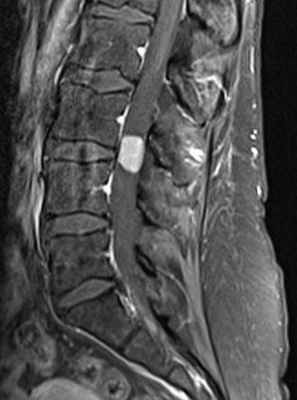

(Справа) Аксиальный срез, Т2-ВИ: объемное образование в просвете правого межпозвонкового отверстия с увеличением объема отверстия и вдавлением тела шейного позвонка. Интраспинальный экстрадуральный компонент опухоли стал причиной выраженного стеноза спинномозгового канала. Опухоль характеризуется преимущественно гиперинтенсивным сигналом с неравномерной гипоинтенсивностью в центральной части. (Слева) На фронтальном Т1-ВИ с КУ визуализируется накапливающее контраст паравертебральное объемное образование на уровне L1-L2 слева, распространяющееся в левое невральное отверстие и минимально оттесняющее дуральный мешок. Ремоделирование костных структур привело к расширению неврального отверстия L1-L2 и истончению корня дуги L1.

(Справа) Аксиальный срез, Т2-ВИ, этот же пациент: зоны гипоинтенсивного Т2-сигнала в центральной зоне опухоли с гиперинтенсивным сигналом по периферии. Это симптом мишени, являющийся неспецифическим признаком, однако встречающийся чаще при нейрофибромах, чем при шванномах.

МРТ поясничного отдела позвоночника. Нейрофиброматоз тип I. Множественные нейрофибромы (стрелки). Сагиттальная и поперечная Т1-взвешенные МРТ с контрастированием, корональная Т2-взвешенная МРТ.